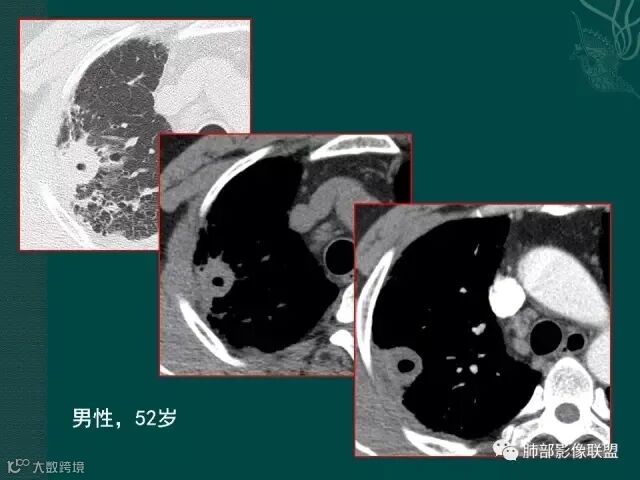

大片液化坏死,内多发空泡,初学者可能感觉是感染,但红箭头所指洞壁虽然不很厚,但仍可见到边界不清的低密度区,黄箭头所指病变侵犯胸膜。

病史似乎是炎性;空洞型病变,靠近纵隔的时候,一定要看对纵隔是否有侵蚀,这是相当重要的。

红箭头所指是右上肺静脉,起始部是完好的,上一层被病变完全包埋,管腔变窄,管壁形态不规则,并侵犯相邻纵隔。

肺癌靠近纵隔时,对纵隔的侵犯,对诊断有重要诊断价值,炎症的话很少会侵犯血管。

厚壁,大部分坏死,外缘较清晰,穿刺时千万不要穿坏死区;

鳞癌破坏力在所有类型肺癌中,都是最强的,所以出现坏死的几率特别是大片坏死的概率,是远远高于腺癌。